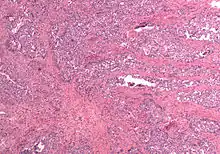

Carcinosarcoma of the uterus

In gross appearance, MMMTs are fleshier than adenocarcinomas, may be bulky and polypoid, and sometimes protrude through the cervical os. On histology, the tumors consist of adenocarcinoma (endometrioid, serous or clear cell) mixed with the malignant mesenchymal (sarcoma) elements; alternatively, the tumor may contain two distinct and separate epithelial and mesenchymal components. Sarcomatous components may also mimic extrauterine tissues (e.g., striated muscle, cartilage, adipose tissue, and bone). Metastases usually contain only epithelial components.